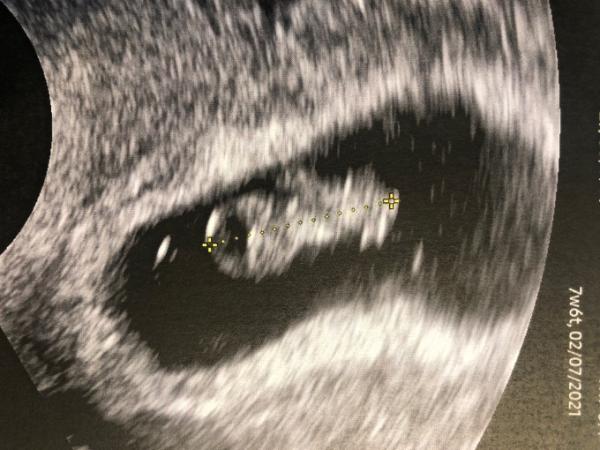

Danke euch für eure Unterstützung Baby ist weiter fleißig gewachsen und ist schon 15mm groß sieht schon fast nach einem kleinen Menschen aus könnte grade nicht glücklicher sein

Bild zu

Danke euch euch auch allen ganz tolle US Termine und hoffentlich nur gute Infos! Meine Fruchthöhle ist immer noch unförmig, der FA sagte aber ihn interessiert das ehrlich gesagt kaum, weil nichts nach Bilderbuch verläuft und Baby wächst ja ordentlich bisher